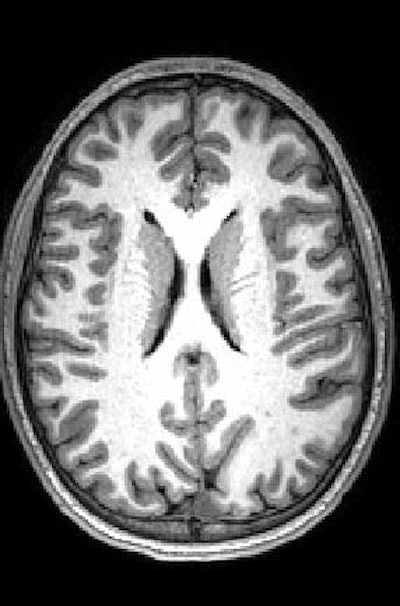

The subjects underwent MRI scans that included arterial spin labeling (ASL) to measure blood flow through the vessels of the brain. They also underwent MR spectroscopy to measure the level of N-acetylaspartate (NAA), an amino acid byproduct commonly used as a marker of healthy neurons. The rate of blood flow is particularly important because active parts of the brain need the most oxygen and nutrients to function properly.

Peterson and colleagues found increased blood flow or hyperperfusion -- indicating more brain activity -- throughout large portions of white matter in the subjects with autism spectrum disorder. This heightened rCBF also correlated with ADOS scores. In other words, hyperperfusion was associated with more severe autism.

Results from NAA analyses also support the compensation theory. Lower NAA concentrations among autistic subjects correlated with higher perfusion at those points in the brain. To put it another way, areas with the lowest levels of healthy neurons exhibited the highest brain activity and blood flow.